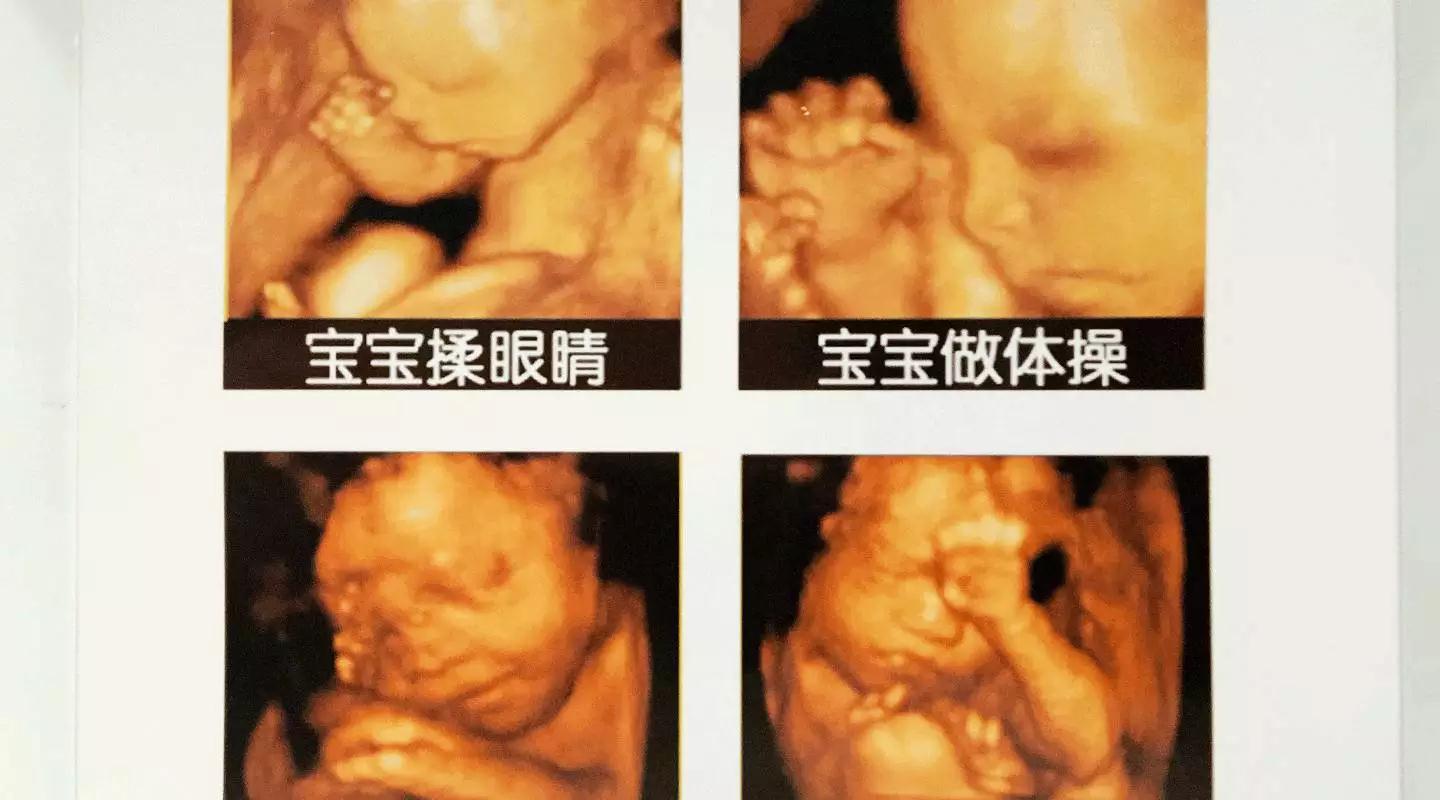

美GE不仅能提供包括腹部、血管、小器官、产科、妇科、泌尿科、新生儿和儿科等多领域的多方面的应用,而且能够显示未出生的宝宝的实时动态活动图像,为胎儿进行宫内拍“写真”和动态录像,让宝宝拥有完整的0岁相册。通过四维彩超(四维彩超),可以看到宫内胎儿打哈欠、伸懒腰、吮手指等萌萌的动作,让准爸妈们增添了安心和乐趣,不再仅仅是感觉宝宝的呼吸和运动,可以亲眼目睹宝宝的举动和乖巧容颜。还可以打印宫内高清写真,作为送给未来宝宝的珍贵礼物!

四维彩超(四维彩超)

宝宝的0岁照片